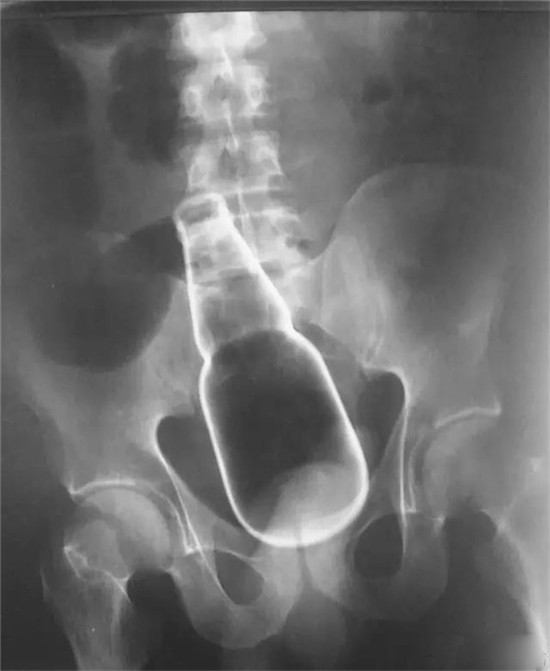

塞进直肠的灯泡。这个是女性病人。

塞进直肠的灯泡。

灯泡大头先塞进去,自己根本就取不出来。

也是一个白炽灯灯泡,是小头先塞进去。看出来男女了吗?

类似的还有圆形的球类的异物。

这是一个直径8厘米的玻璃圆球。

直肠里塞了灯泡或者圆球,是肛门自慰人群的常见意外。

要取出灯泡,需要肛门充分松驰,才能取出来。可以在肛门处打局麻,但是效果不好,不够松,可以打腰麻或者硬麻,当然,最好是全麻,就可以有满意的肛门松驰。

上面图片是产钳,从直肠里把直径8厘米的圆球拽出来。

只要产钳能够夹住灯泡或者圆球,把肛门扩大,可以轻松把灯泡拽出来。不用担心灯泡会碎了。当然,为了保险起见,可以在直肠与肛门处打 润滑油如石蜡油,有润滑后,会更容易拽出来。